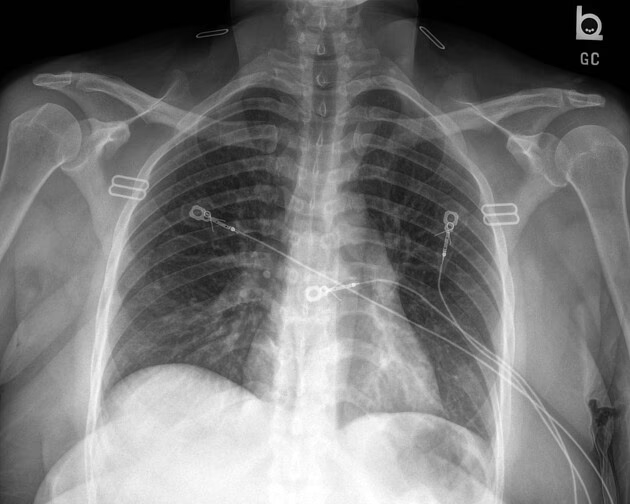

- Matglasforandringer (Ground-Glass Opacities - GGO): Dette er det hyppigste fund. På en CT-scanning ser det ud som tågede eller slørede områder i lungerne, hvor man stadig svagt kan ane de underliggende blodkar og luftveje. Disse forandringer indikerer en delvis fyldning af lungeblærerne (alveolerne) med væske, celler eller andet materiale, hvilket reducerer luftindholdet. Matglasforandringer kan være spredt i små pletter eller dække større, sammenhængende områder.

- Konsolidering: Dette refererer til områder i lungen, hvor lungeblærerne er helt fyldt med inflammatorisk materiale (væske, pus, blod), hvilket gør lungevævet tæt og solidt. På en CT-scanning fremstår konsolidering som helt hvide, uigennemsigtige områder, hvor de normale lungestrukturer ikke længere kan ses. Dette er ofte et tegn på en mere alvorlig lungebetændelse.

- Kombination af matglas og konsolidering: Det er meget almindeligt at se en blanding af begge mønstre. Ofte kan et område starte som matglas og udvikle sig til konsolidering, efterhånden som inflammationen forværres.

- Fordeling i lungerne: Mønstrene ved influenza har ofte en tendens til at være placeret peribronkovaskulært (omkring luftvejene og blodkarrene) og subpleuralt (lige under lungehinden). Fordelingen er typisk multifokal og plettet, hvilket betyder, at den optræder flere steder i begge lunger.

Et af de mest overraskende og vigtige punkter er, at en CT-scanning kan være fuldstændig normal hos en patient med en bekræftet influenza-infektion. Studier har vist, at dette kan være tilfældet i op til halvdelen af patienterne, især dem med mildere symptomer, hvor infektionen primært er begrænset til de øvre luftveje. En normal CT-scanning udelukker altså ikke influenza, men det indikerer, at der ikke er udviklet en signifikant lungebetændelse, som er synlig på scanningen. Dette understreger, at diagnosen altid skal baseres på en kombination af symptomer, klinisk undersøgelse og laboratorietests (f.eks. en podning).

Et almindeligt røntgenbillede er ofte den første undersøgelse, men det er mindre følsomt end en CT-scanning. Milde forandringer som lette matglasforandringer kan være usynlige på et røntgenbillede. En CT-scanning giver et langt mere detaljeret billede af forandringernes type, placering og omfang.